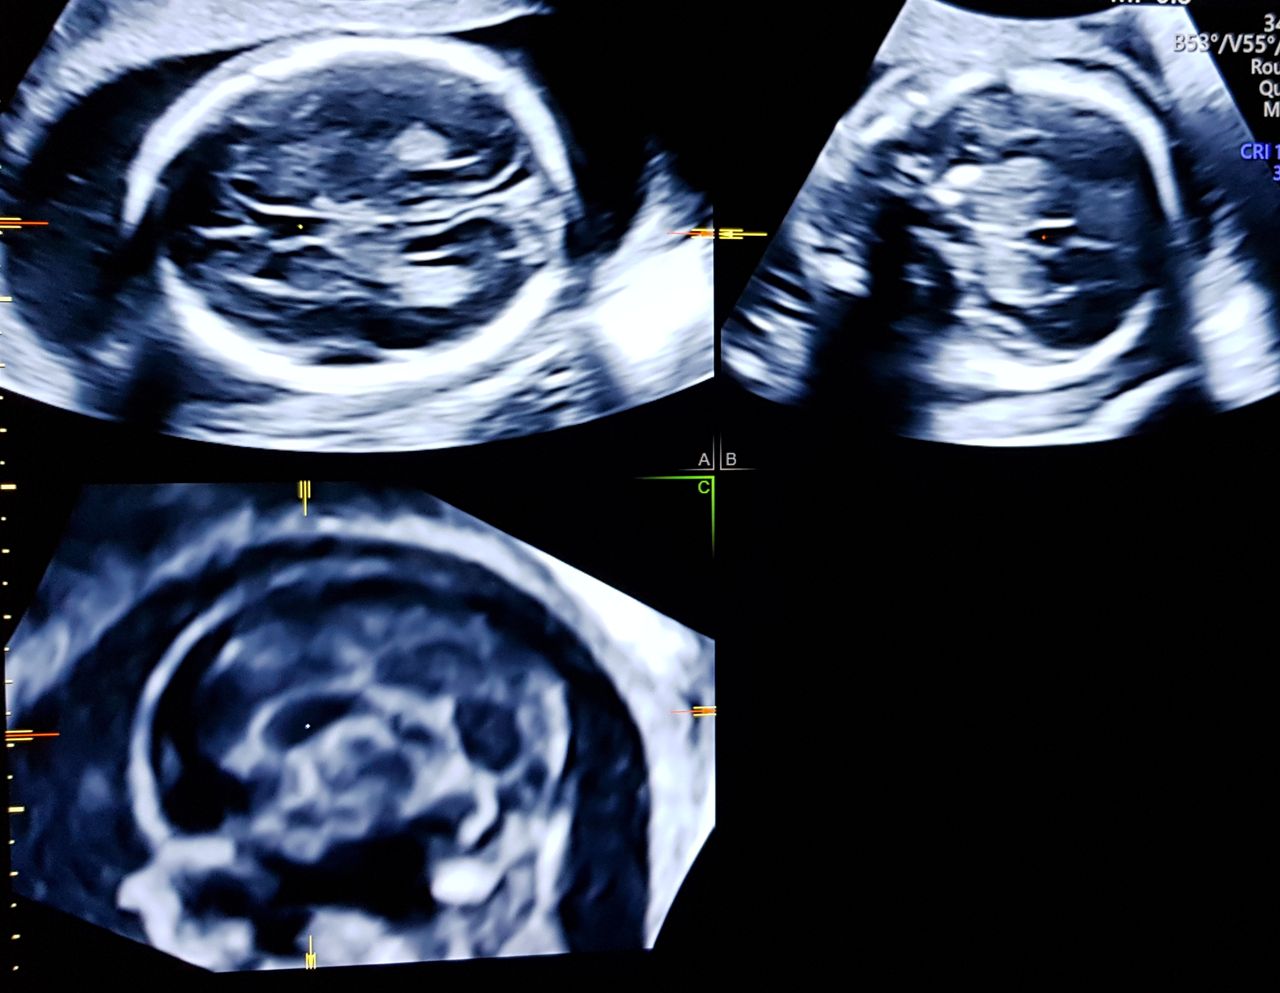

Foto e video

4- Nadia Fichera 1, Vito Leanza 1, Morena Maria Monteleone 1, Giuliana Chiara Maugeri 1, Gianluca Leanza 2, Antonio Carbonaro 1, Salvatore Carbonaro 3, Maria Giovanna Verzì 1, Marco Antonio Palumbo 1 Corpus callosum agenesis: prenatal diagnosis and neurodevelopmental outcome. European Gynecology and Obstetrics. 2020; 2(4):205-209

• Studio Ginecologico- Dott.ssa Nadia Fichera ecocardiografia fetale  •